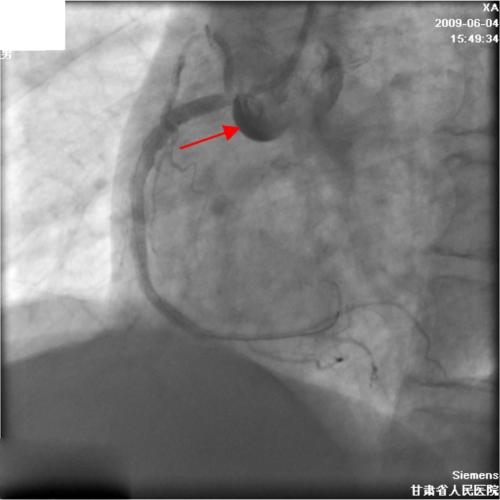

右冠状动脉经皮介入治疗期间对瓦氏窦冠状窦的广泛解剖——病例报告及文献综述

Extensive dissection to the coronary sinus of valsalva during percutaneous intervention in right coronary artery-a case report and literature review.

Severe retrograde dissection extending into the sinus of Valsalva is a rare complication during percutaneous coronary intervention (PCI), but life threatening. There is some literature about this complication, but this particular complication has not been previously reported in China. We present a case of coronary artery dissection during a PCI in which progressively extended retrogradely into the sinus of valsalva, and was successfully treated with stenting without an operation.

摘要

严重的逆行性夹层扩展至主动脉瓣窦是经皮冠状动脉介入治疗(PCI)期间罕见但危及生命的并发症。关于这一并发症有一些文献报道,但在中国此前尚未报道过这种特殊的并发症。我们报告一例PCI期间冠状动脉夹层病例,该夹层逐渐逆行扩展至主动脉瓣窦,并成功通过支架置入治疗,未进行手术。